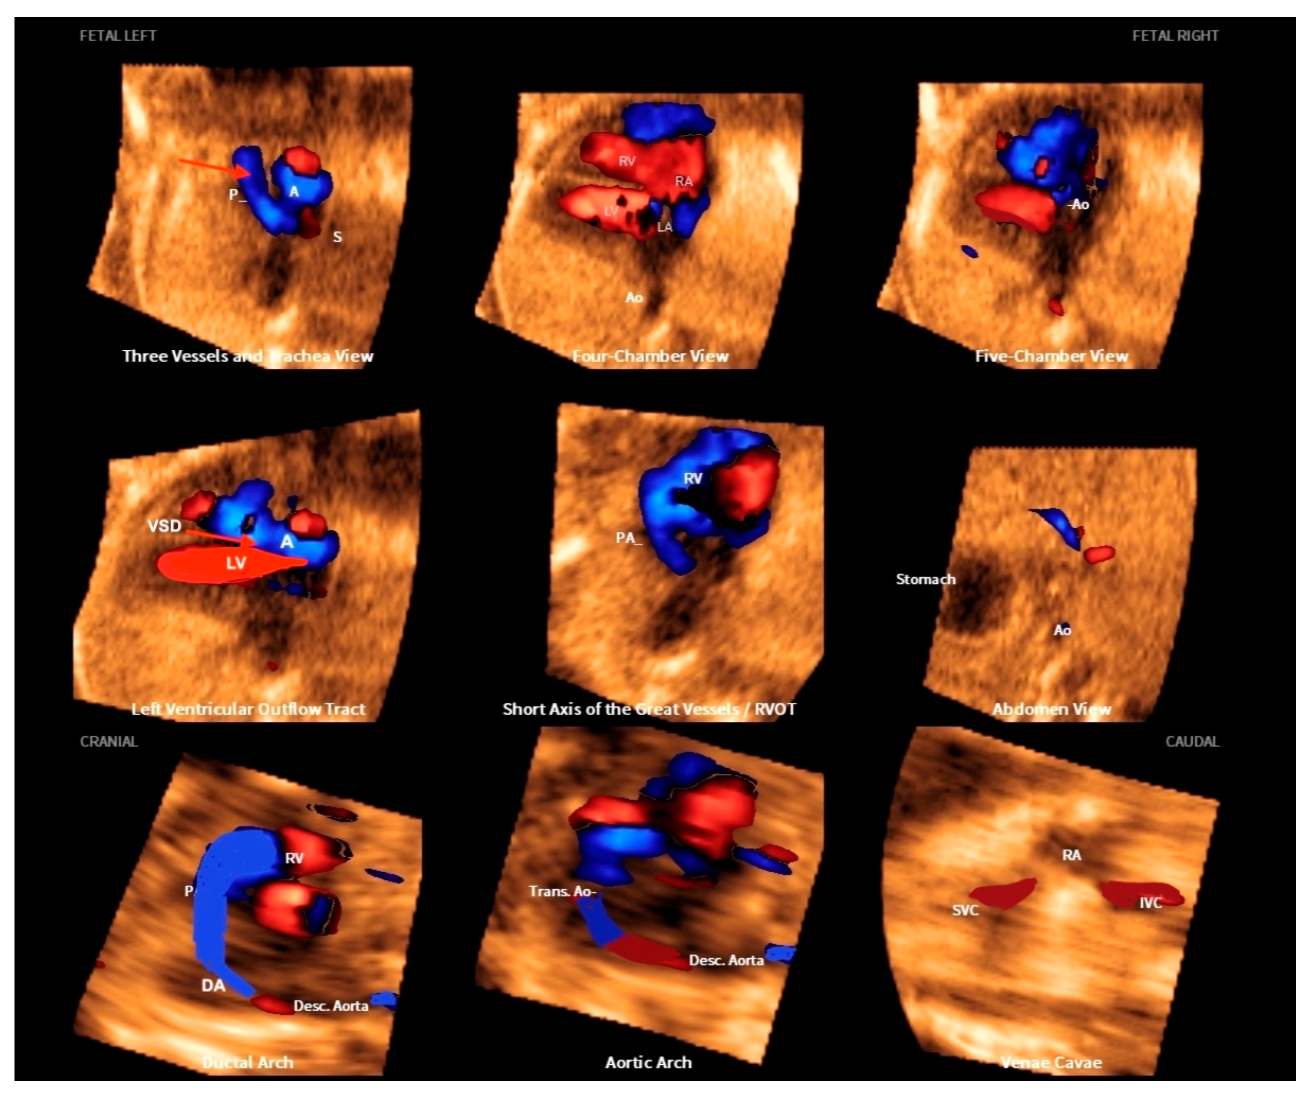

9. Tetralogy of Fallot

- Malho, A.S.; Bravo-Valenzuela, N.J.; Ximenes, R.; Peixoto, A.B.; Araujo Júnior, E. Antenatal diagnosis of congenital heart disease by 3D ultrasonography using spatiotemporal image correlation with HDlive Flow and HDlive Flow silhouette rendering modes. Ultrasonography 2022, 41, 578–596. [Google Scholar] [CrossRef] [PubMed]